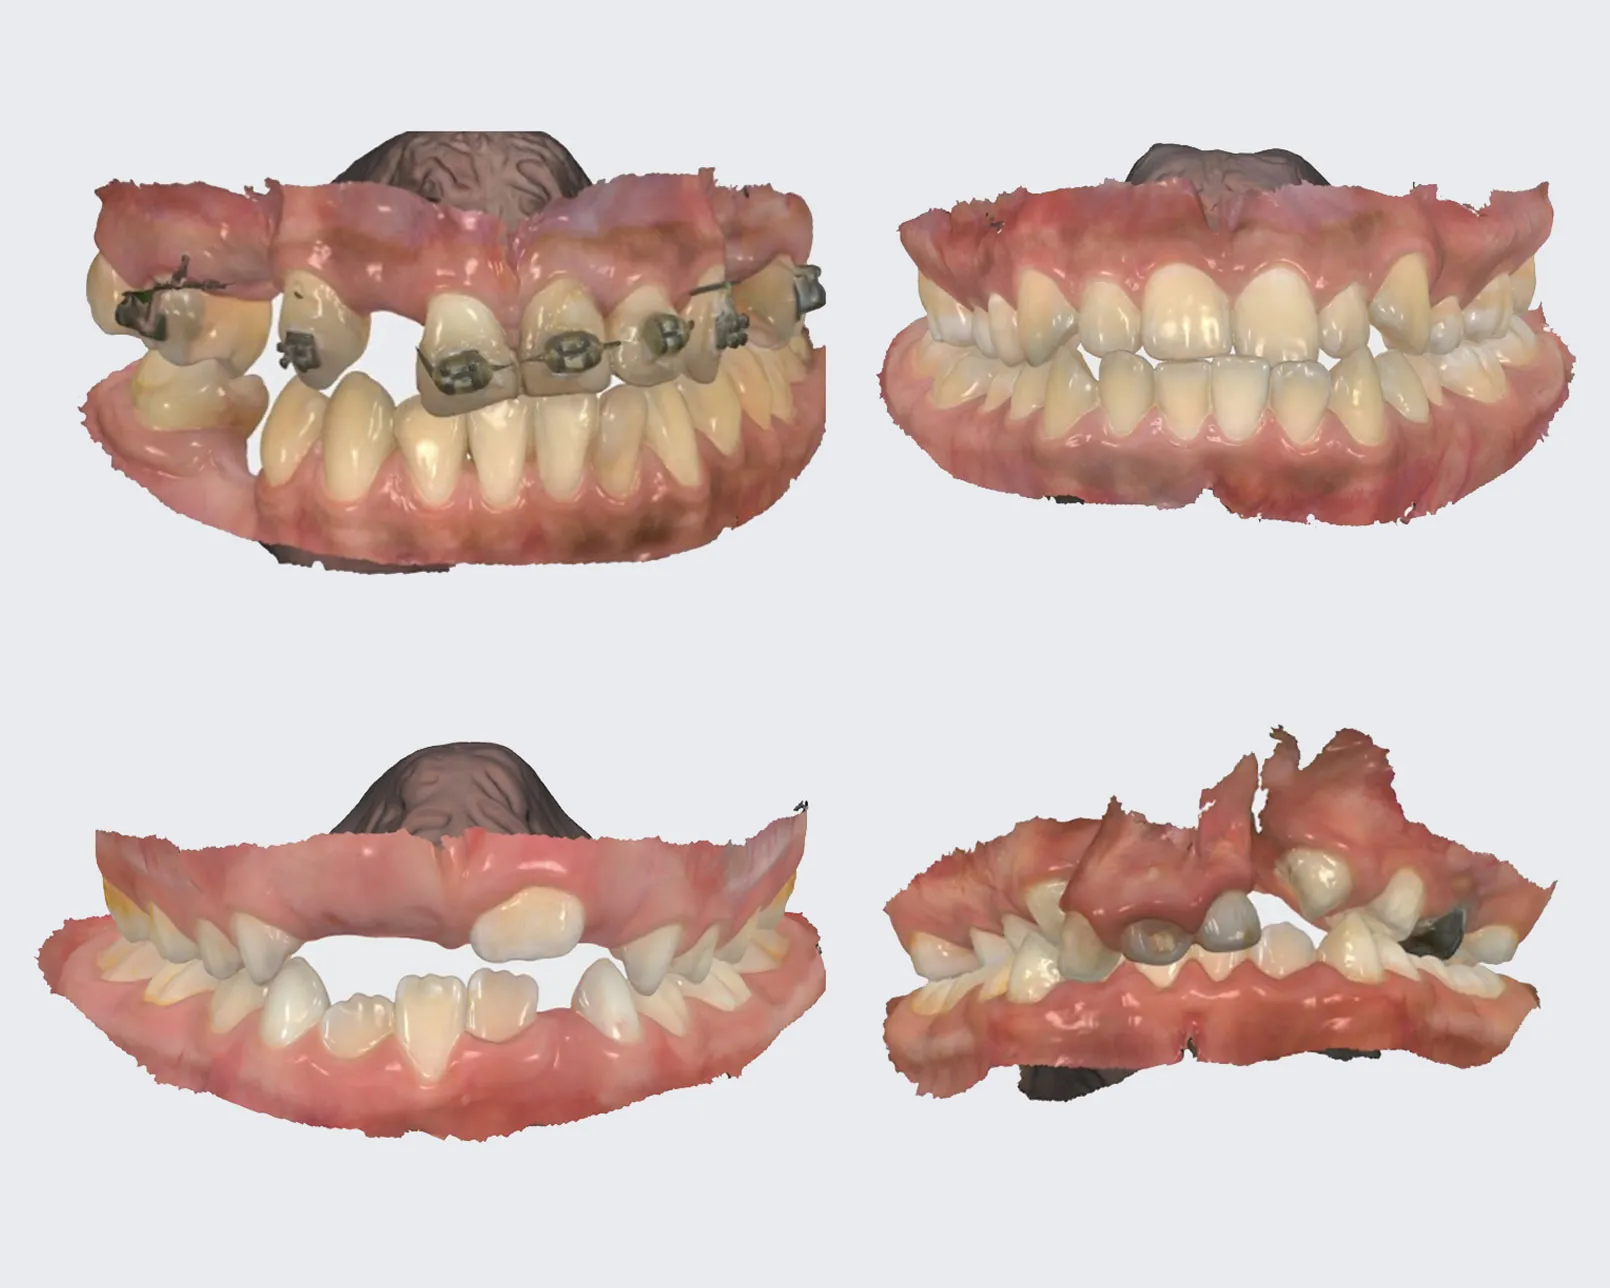

ESCANEO INTRAORAL

Con nuestro escáner de la marca 3Shape captura impresiones directamente sobre la dentadura obteniendo una imagen en 3D, eliminando el sistema tradicional de impresiones físicas realizadas con alginato.

IMPRESIONES 3D

Modelos dentales en un tiempo más corto y con mayor precisión, lo que beneficia tanto a los pacientes como a los profesionales.

Escaneo de maxilar superior e inferior indicado para tratamiento de ortodoncia.